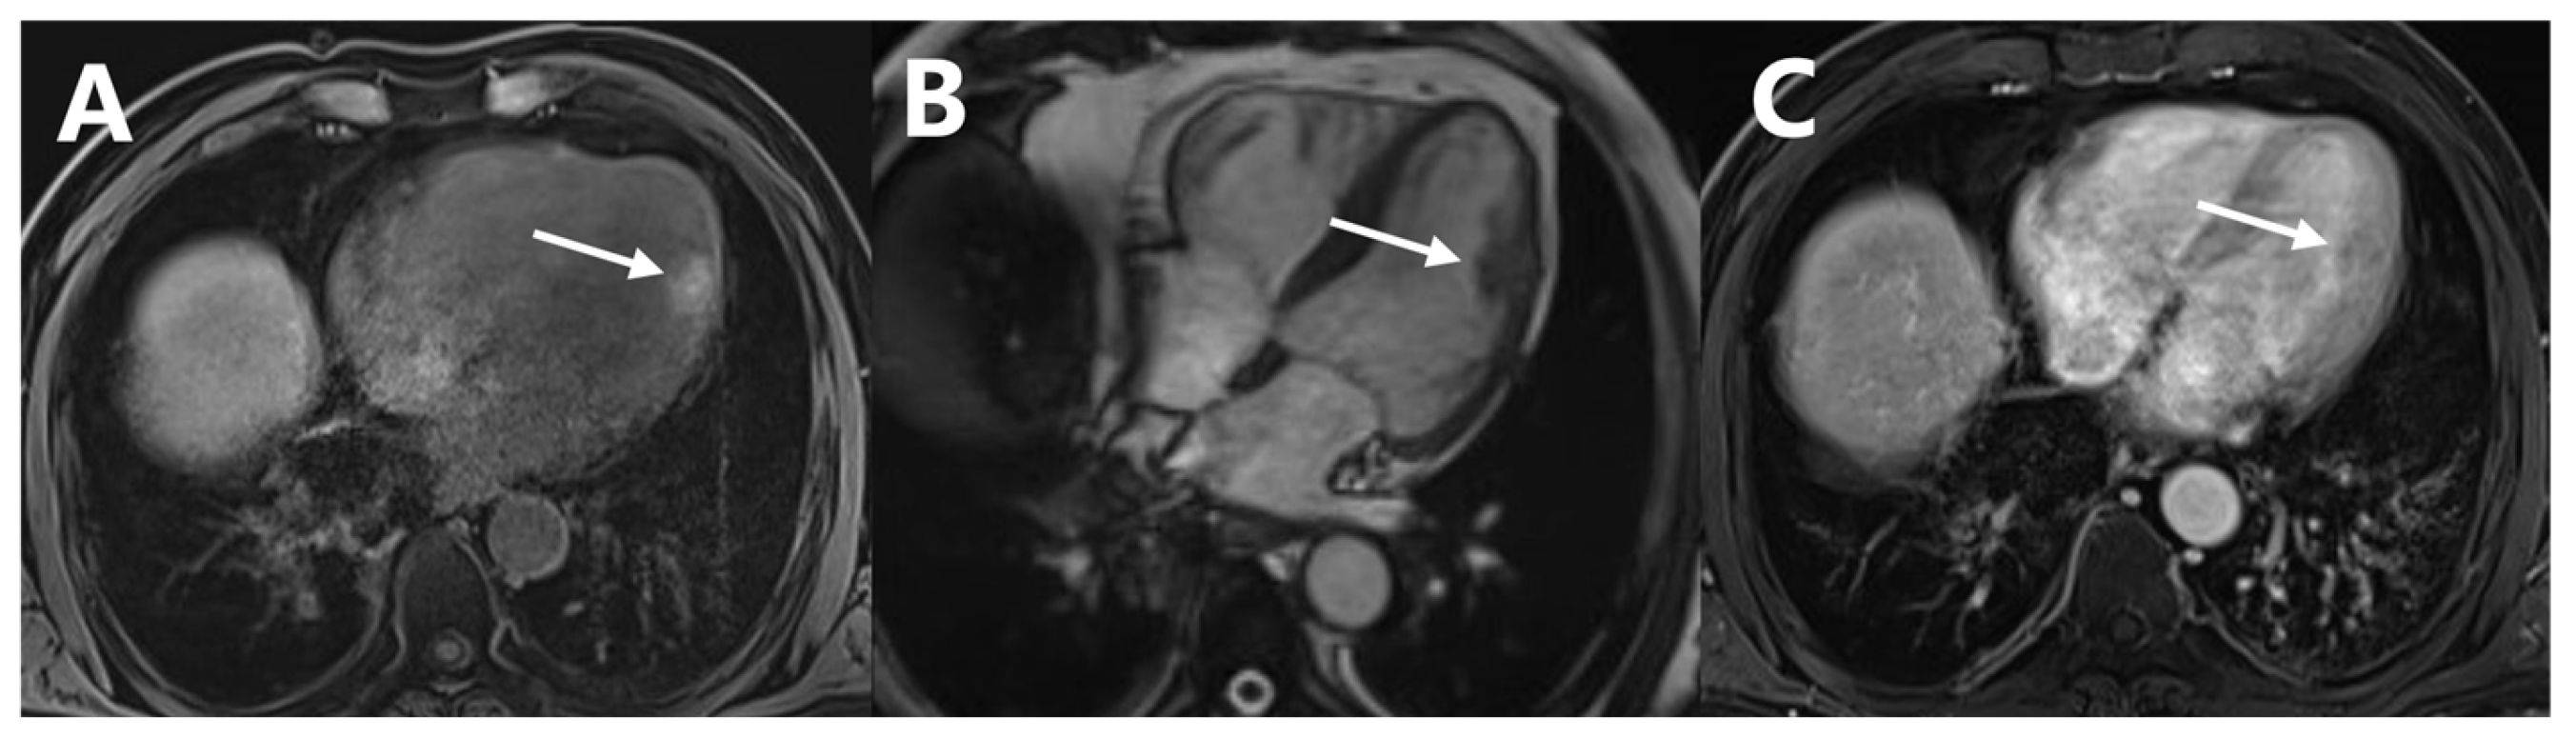

Cardiac Metastasis of Malignant Melanoma Detected by 18F-FDG PET/CT